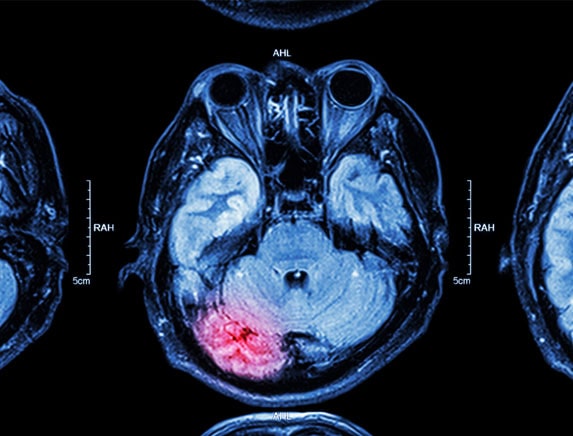

Brain Tumor Surgery

Brain Tumor Surgery is one of the most serious operations in the medical sciences. As there are many complications related to this type of surgery, only the best neurosurgeon in Delhi should be trusted for the same. Surgeons have to be very careful while trying to limit the problems during and after the surgery, This surgery requires making an opening in the skull, which if not done properly can lead to bleeding, infections and rare reactions. Dr. Sumiet snha is a proficient neurosurgeon in India for brain tumor surgery.